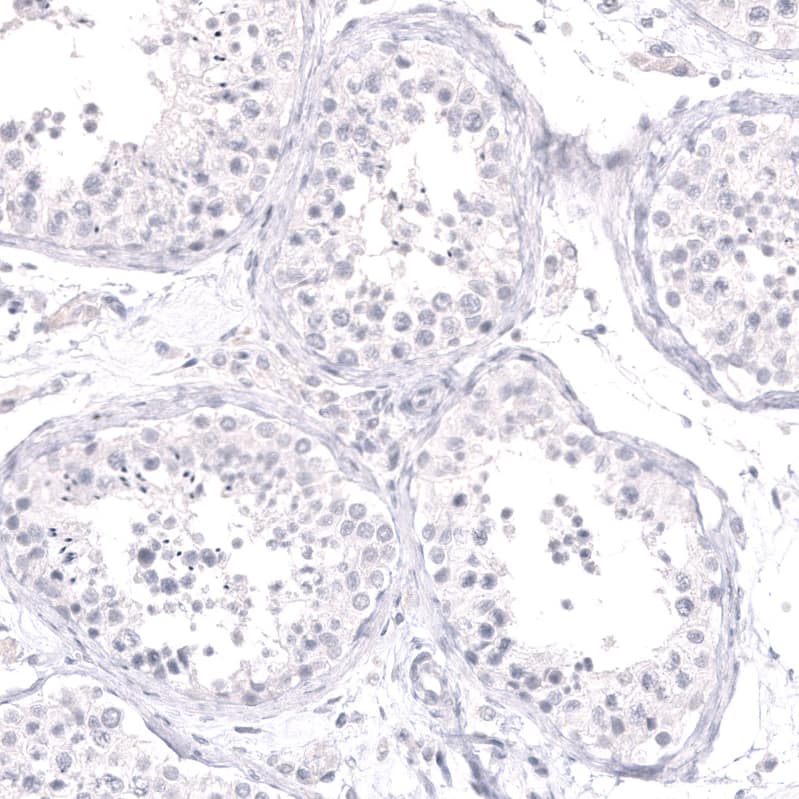

Staining of human testis shows no positivity in cells in seminiferous ducts as expected.